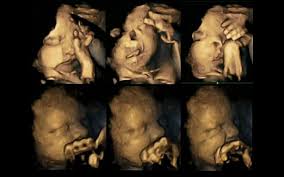

Εναν συγκλονιστικό τρόπο για να αναδείξουν τις βλαβερές συνέπειες του καπνίσματος για τα έμβρυα βρήκαν οι επιστήμονες: τις κινήσεις ενόχλησης που κάνουν με τα μικροσκοπικά τους χέρια τα ίδια τα έμβρυα, όπως αυτές εικονίζονται σε υπερηχογραφήματα με τετραδιάστατη απεικόνιση (4D).

Επειτα από ενδελεχή μελέτη των υπερηχογραφημάτων τους κατά την 24η, την 28η, την 32η και την 36ή εβδομάδα της κύησης, παρατήρησε ότι τα έμβρυα των οποίων οι μητέρες κάπνιζαν έκαναν πολύ περισσότερες επαναλαμβανόμενες κινήσεις με το στόμα τους ή άγγιζαν τον σώμα τους απ’ ότι τα έμβρυα των οποίων οι μητέρες δεν κάπνιζαν.

Συνήθως τα έμβρυα κουνούν λιγότερο το στόμα τους και αγγίζουν το σώμα τους κατά τις τελευταίες εβδομάδες της κύησης.